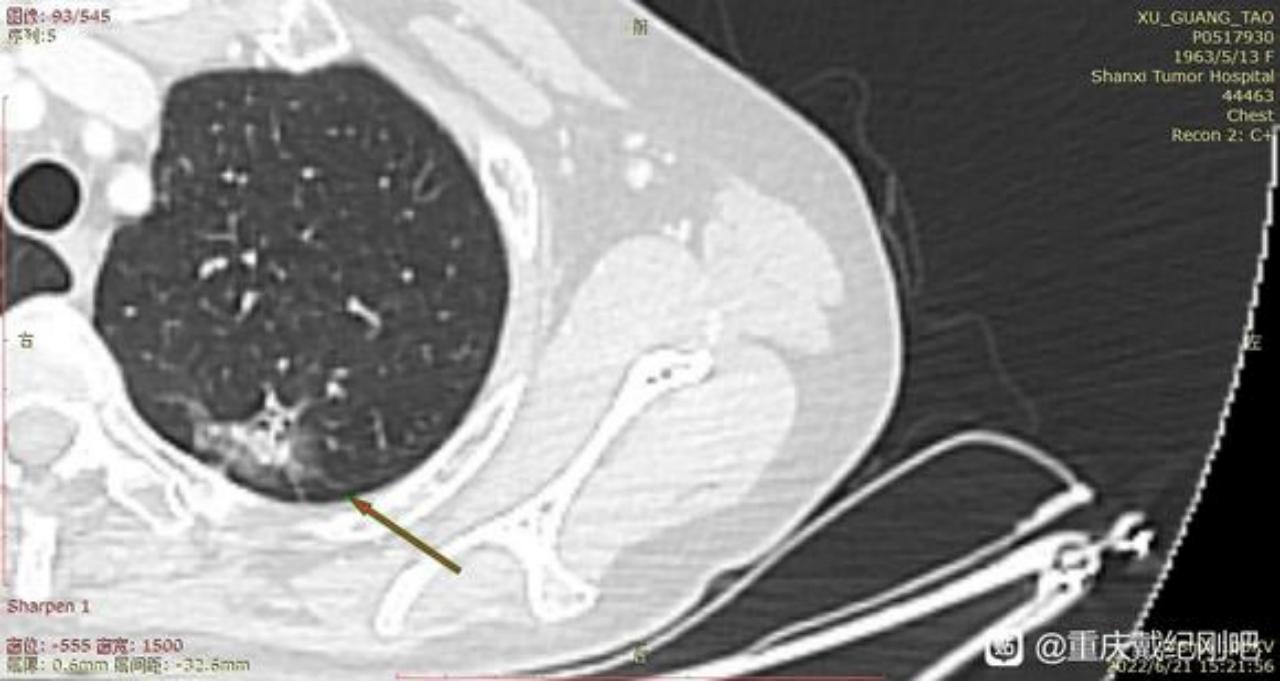

主任前段时间已经麻烦过您了,术后病例确实跟您的判断一样,左肺上叶结节为早期肺腺癌(腺泡型)。当时我们医生先是进行了楔形切除,中间又出来谈话进行了叶切。(患者我母亲,59岁女性,不抽烟喝酒)现在术后病例出来了:腺泡型肺腺癌、大小2cm*1.5cm*1cm,支气管、淋巴结未见累计。

3、主任,根据您之前判断,右肺下页的0.7毫米磨玻璃结节至少是微浸润。现在医生给切了左肺上叶,后面手术多久能进行啊?是不是难度很大了?